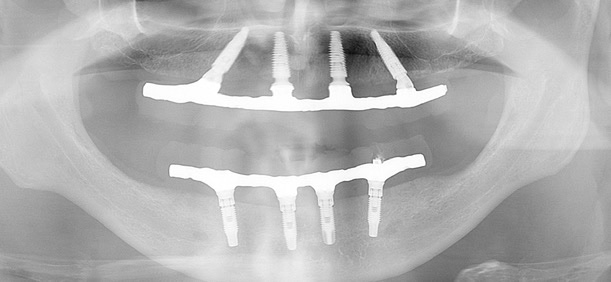

Radiografia All-on-Four Bimaxilar